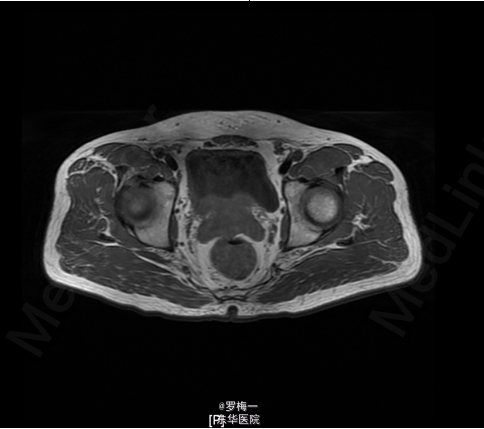

住院后完善相关检查,PSA两项均升高,其他各项术前常规检查未见明确手术禁忌证。遂于2015-04-02行经直肠前列腺穿刺活检,病理提示“符合前列腺增生伴慢性炎”。盆腔MR平扫+增强扫描考虑膀胱癌复发可能性大;彩超肝胆胰脾及核素骨扫描暂未见肿瘤远处转移证据。